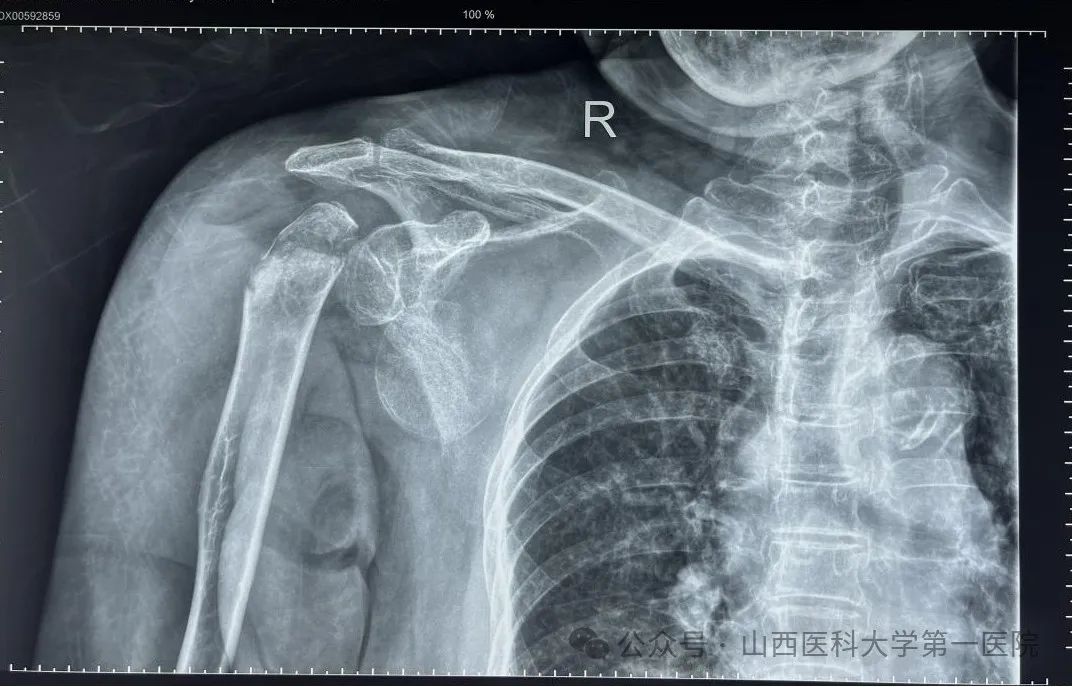

患者因摔倒致右肩、左腕部、右髋部疼痛伴活动受限3日余就诊于山医大一院骨科,入院诊断为:右肱骨近端粉碎骨折合并右肩关节脱位;左桡骨远端、腕骨、尺骨骨折;骨盆骨折。多处骨折尤以肩关节最为严重,术前影像学资料显示患者右侧肱骨近端粉碎骨折,肱骨头完全脱位卡在肩胛盂下方。

术前影像学检查结果